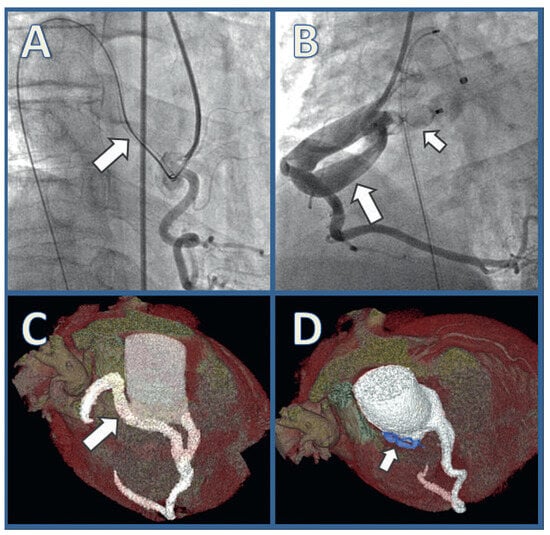

Transcatheter Closure of a Large Right Coronary Artery Fistula in a Patient with Bacterial Endocarditis

by Stefan Toggweiler, Jonathon Leipsic, Namal Wijesinghe and Ronald G. Carere

Cardiovasc. Med. 2011, 14(3), 105; https://doi.org/10.4414/cvm.2011.01574 - 23 Mar 2011

This 45-year-old male, generally healthy patient was hospitalised with sepsis, due to endocarditis with a right atrial vegetation [...] Full article